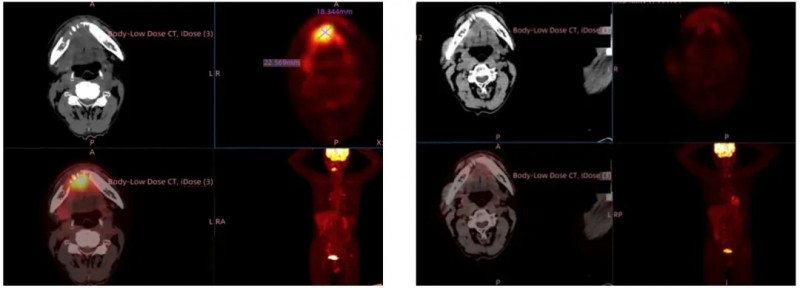

此前公布的典型案例显示,1例部分缓解(PR)患者的左侧锁骨上窝Virchow淋巴结(治疗前46.7mm),经GT201治疗4个月后缩小69%(详见下图)。

▲图源“ASCO”,版权归原作者所有,如无意中侵犯了知识产权,请联系我们删除

结果显示:TIL输注后仅3周,患者病灶显著缩小达临床部分缓解(PR);治疗9周随访时,影像学评估显示所有病灶完全消失,成功达到完全缓解(CR)(详见下图)。

▲图源“上海九院官网”,版权归原作者所有,如无意中侵犯了知识产权,请联系我们删除